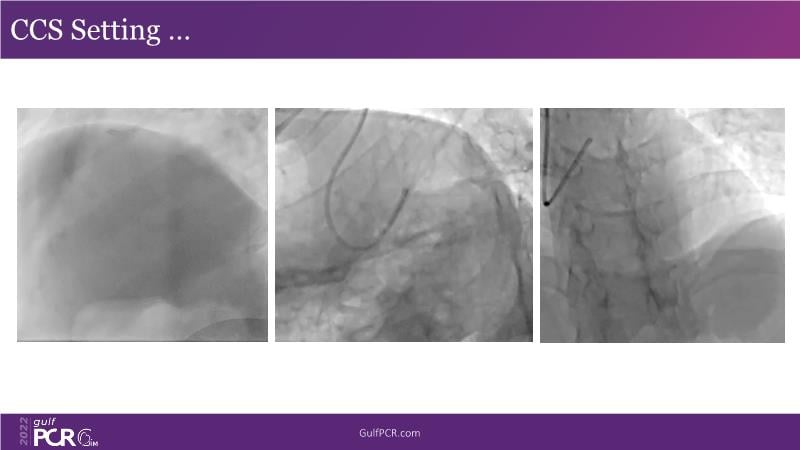

In this session, follow a LIVE case from the Chest Diseases Hospital in Kuwait and learn what the best strategy is to treat patients who present with a very long calcified coronary artery lesion, as well as how to select the best device and which different types of stents can be used.